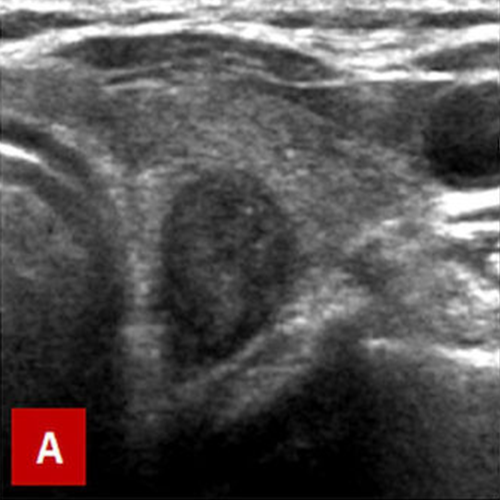

Typical ultrasound features of papillary carcinoma: A. Taller than wide and hypoechoic appearance, large size. B. Irregular contours, large size, microcalcifications (white spots) and hypoechogenecity. C. Large size and increased central vascularity on color Doppler ultrasound. If these features are present on ultrasound, probability of cancer is considered high and a fine needle aspiration biopsy (FNAB) should be performed.